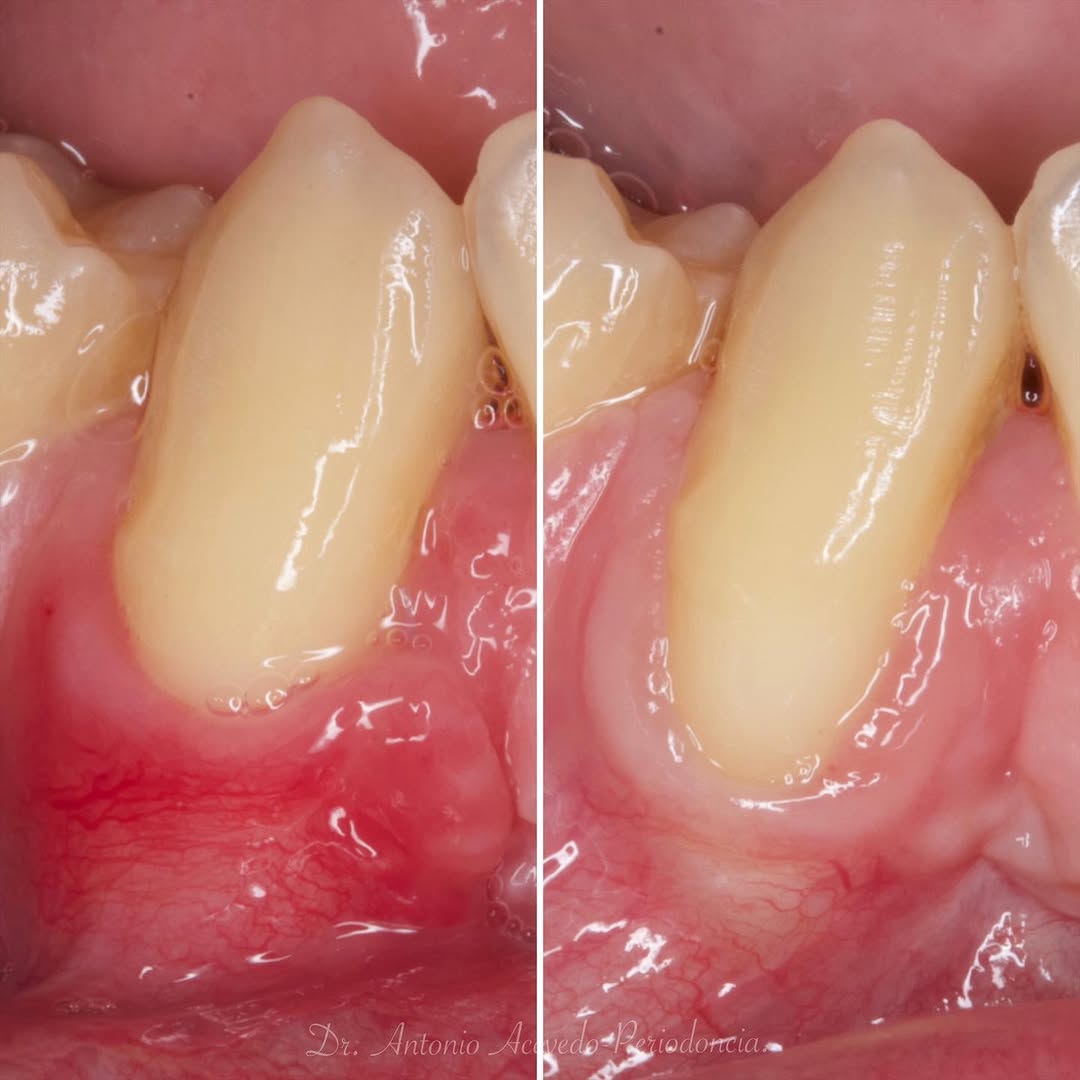

Se presenta un caso clínico de restauración directa en resina composite, ejemplo del valor de la precisión y la técnica meticulosa incluso en procedimientos considerados rutinarios dentro de la práctica diaria. El caso pone en evidencia la importancia del control de la morfología, la textura y la integración cromática, así como del adecuado aislamiento del campo operatorio y la estratificación del material, factores determinantes para conseguir un resultado natural, funcional y duradero. A través de una ejecución cuidadosa, se logró una restauración estéticamente imperceptible y funcionalmente estable, que respeta los principios de mínima invasión y adhesión efectiva. Este tipo de procedimientos, aunque cotidianos, reflejan la constancia y el nivel de exigencia clínica necesarios para ofrecer odontología de calidad en todos los casos, independientemente de su complejidad.